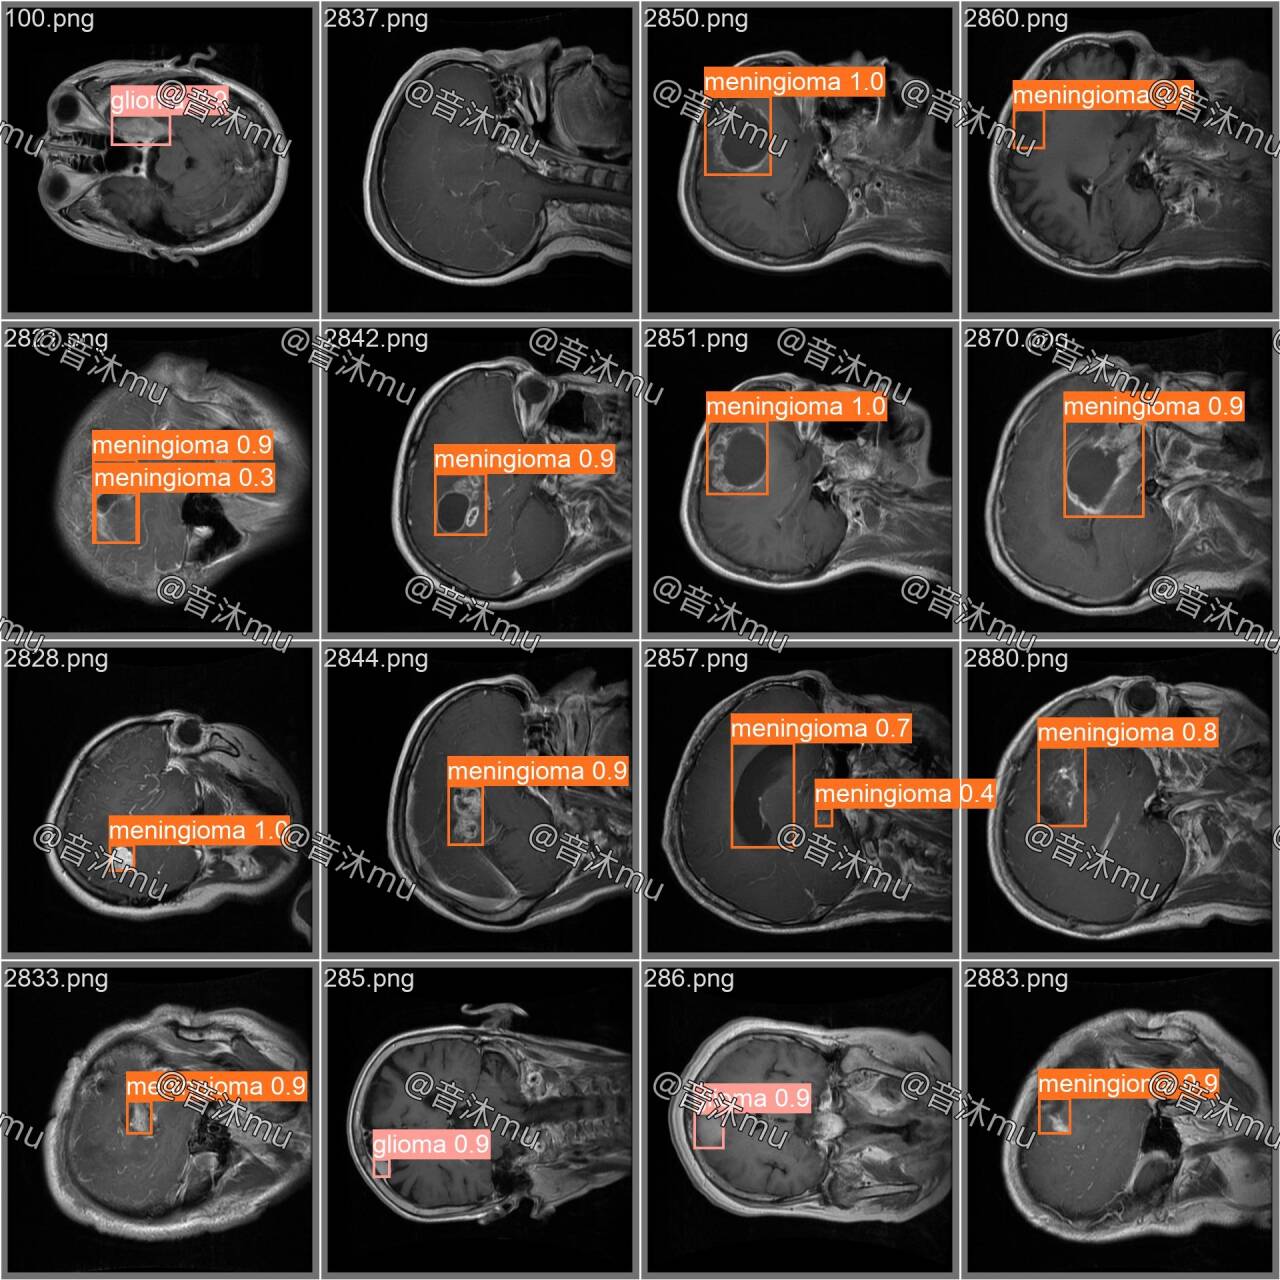

①pituitary tumor(垂体瘤)

②meningioma(脑膜瘤)

③glioma(神经胶质瘤)

有yolov5-v7.0训练好的模型结果 (训练100轮、预训练模型yolov5s.pt、mAP0.935)

有yolov8训练好的模型结果 (训练100轮、预训练模型yolov8n.pt、mAP0.936)